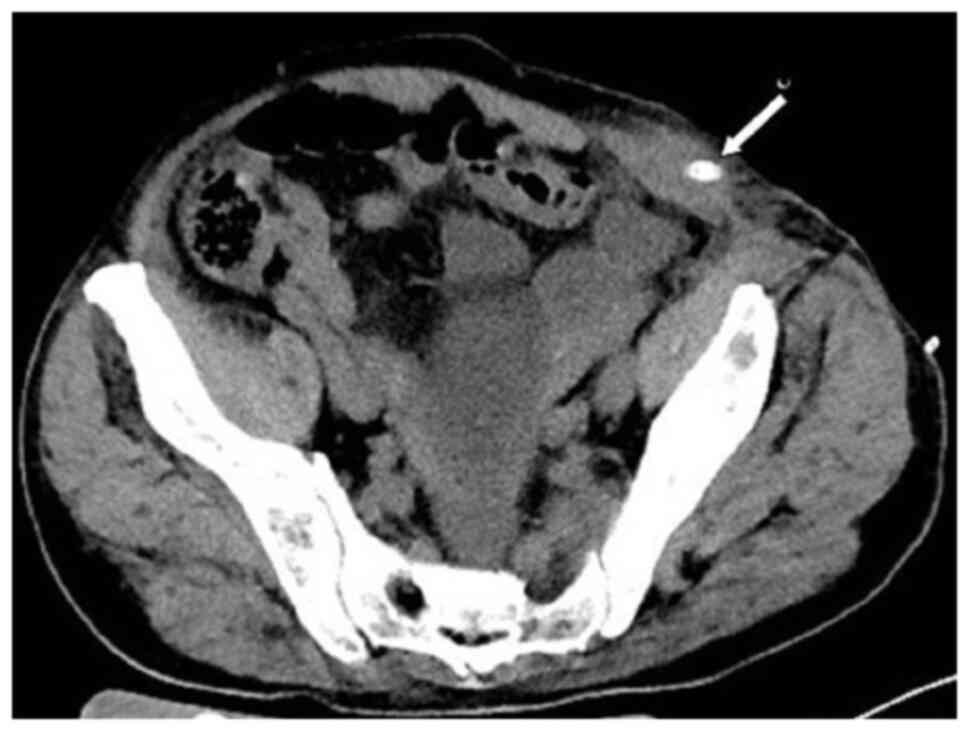

Subsequently, the patient presented with a lump around the colostomy stoma site and intermittent abdominal pain in November 2020. Physical examination revealed a lump measuring ~10×10 cm around the stoma, which did not reduce in size when the patient was lying flat. Abdominal CT (Fig. 4) revealed that the intestinal tube had protruded into the subcutaneous fat layer of the abdomen. Based on the patient's medical history, physical examination (a lump around the colostomy stoma site) and the result of abdominal CT (Fig. 4), a parastomal hernia was suspected. Surgery was the recommended treatment. Routine preoperative blood tests, coagulation function, and liver and kidney functions showed no abnormalities. Parastomal hernia repair surgery was performed using the keyhole technique in November 2020. A relatively soft drainage tube was placed subcutaneously in the surgical area. The patient recovered well after the surgery and was discharged on the third postoperative day without removing the drainage tube. During discharge, the surgical area was not compressed. However, five days after discharge, the patient experienced swelling, pain and bleeding at the surgical site. Abdominal CT showed a hematoma in the surgical area (Fig. 5). After taking hemostatic treatment measures (hemostatic drugs, compression hemostasis), fresh blood still slowly flowed out from the drainage tube. Dynamic reexamination of coagulation function showed that it gradually deteriorated, and the activated partial thromboplastin time was gradually delayed to 60 sec, which was 20 sec longer than normal (reference range, 20–40 sec). The patient had stubborn anemia, and after multiple blood transfusions, no significant increase was identified in hemoglobin, which remained between 45–68 g/l (normal range, 130–175 g/l). A bone marrow biopsy was also performed to investigate the cause of persistent bleeding (Fig. 6). The bone marrow smear was stained using the Wright staining method and 200 cells were counted under a microscope. The results showed abnormal proliferation of plasma cell lines in bone marrow smears, accounting for 35% of total cells, with an immature plasma cell composition accounting for 21.0% of total cells (normal range, 0–0.8%). This result is consistent with the diagnosis of multiple myeloma (10,11). Fig. 6 shows the characteristics of abnormal plasma cells: This type of cell was significantly different in size, with the cell body and nucleus appearing circular, elliptical, ovoid or irregular in shape. The nucleus was misaligned, the chromatin of the nucleus appeared as a granular or loose network and certain cells showed obvious nucleoli. The cytoplasm was rich, stained opaque dark blue and flame-like, with obvious light staining bands around the nucleus. Nodular protrusions and vacuoles were easily observed, while no particles were seen. The morphological features were consistent with those of MM (10). Further testing revealed elevated serum immunoglobulin A (IgA) levels of 76.7 g/l (normal range, 0.82–4.53 g/l) and significantly increased serum β2 microglobulin (β2-microglobulin) levels of 16,205 ng/ml (normal range, 604–2,286 ng/ml). Based on the results of the bone marrow puncture, the bone destruction, anemia and bleeding were attributed to MM. After consultation with a hematologist, the patient was diagnosed with MM (IgA-λ type, Durie-Salmon Stage III). The Durie-Salmon staging system is a classic staging system for MM. The staging criteria for Stage III are as follows: One or more of the following abnormalities must be present: Hemoglobin <8.5 g/dl; serum calcium >12 mg/dl; very high myeloma protein production; IgG peak >7 g/dl; IgA peak >5 g/dl; Bence Jones protein >12 g/24 h; and >3 lytic lesions on bone survey (11). The patient was transferred to the hematology department and was treated with the PCD regimen (bortezomib, cyclophosphamide, dexamethasone), chemotherapy and blood transfusion. The specific dosage of medication is calculated based on the patient's body surface area. One chemotherapy cycle is 4 weeks and this patient received 6 cycles of chemotherapy. Afterwards, the patient received maintenance treatment with bortezomib monotherapy. The seventh rib lesion invaded the surrounding soft tissue, and the interventional department performed an empty needle puncture biopsy on it. The pathological and immunohistochemical results of the puncture tissue are consistent with multiple myeloma (10). The lesion was determined to be plasmacytoma, suggesting involvement of MM (Fig. 7), and the immunohistochemical results were as follows: CD138 (+), CD38 (+), cytokeratin (CK) (−), Ki67 (15%, +), Lambda (+) and MM oncogene 1 (+) (Fig. 8). CK negativity indicated the absence of malignant cells of epithelial origin. The patient's condition gradually improved, with increasing hemoglobin levels, recovering coagulation function, absorption of the hematoma around the stoma (Fig. 9) and alleviation of bone pain. For the past 2 years, the patient has been regularly treated in the hematology department and the progression of the MM has been slow (Figs. 10 and 11). Fig. 10 is a PET/CT image of the patient diagnosed with MM one year later. The arrows in Fig. 10 indicate the metabolic status of the lesionsin the right seventh posterior rib, upper sternum, and first lumbar spine. The increased metabolism of these three main lesions is consistent with the manifestation of MM. In Fig. 11, row A represents the situation of lesion in the upper sternum at different time-points; row B shows the situation of lesion in the upper sternum at different time-points; and row C shows the situation of lesion in the upper sternum at different time-points. The arrows in Fig. 11Aa, Ba and Ca refer to the lesions of the upper sternum, the seventh rib on the right side and the first lumbar vertebra when MM was diagnosed. Fig. 11Ab-Cb shows the respective lesions 1 year after the diagnosis of MM and Fig. 11Ac-Cc shows them at 2 years after the diagnosis of MM. After comparison, the progression of these three lesions was not obvious. After treatment, the soft tissue mass around the lesion of the right seventh rib gradually became smaller. The patient has not experienced any worsening bone pain symptoms since being diagnosed with MM. The patient has been regularly visiting the hematology outpatient department. During the follow-up period, the patient's blood routine, coagulation function and serum immunoglobulin are being tested every two months, and chest CT and spinal CT examinations conducted every 6 months. During follow-up, there has been occasional mild anemia but no coagulation abnormalities.

Figure 9.

After the diagnosis of multiple myeloma and treatment, the hematoma (arrow) was significantly absorbed.